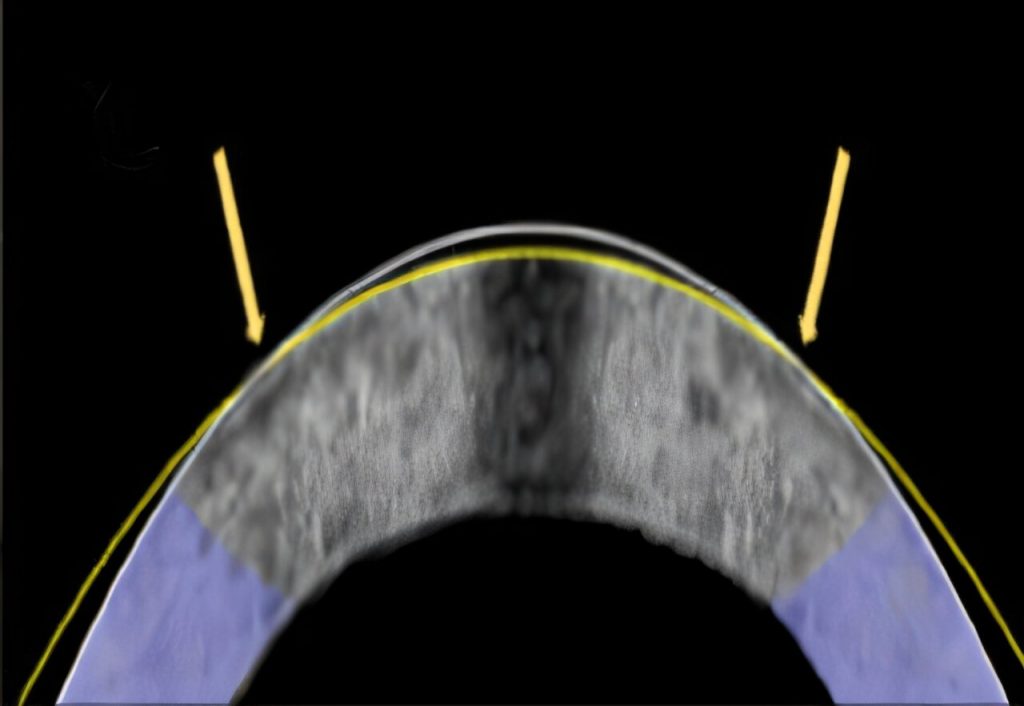

Изменение кривизны роговицы в глазе кролика с помощью нового метода. Изображение: Daniel Kim and Mimi Chen

Метод протестировали на 12 извлеченных глазах кроликов. Десять из них были успешно модифицированы для имитации коррекции близорукости. После кратковременного воздействия тока каждая роговица приняла форму, заданную электродом-линзой. Процедура заняла около минуты, при этом ученые не обнаружили повреждений ткани или гибели клеток.